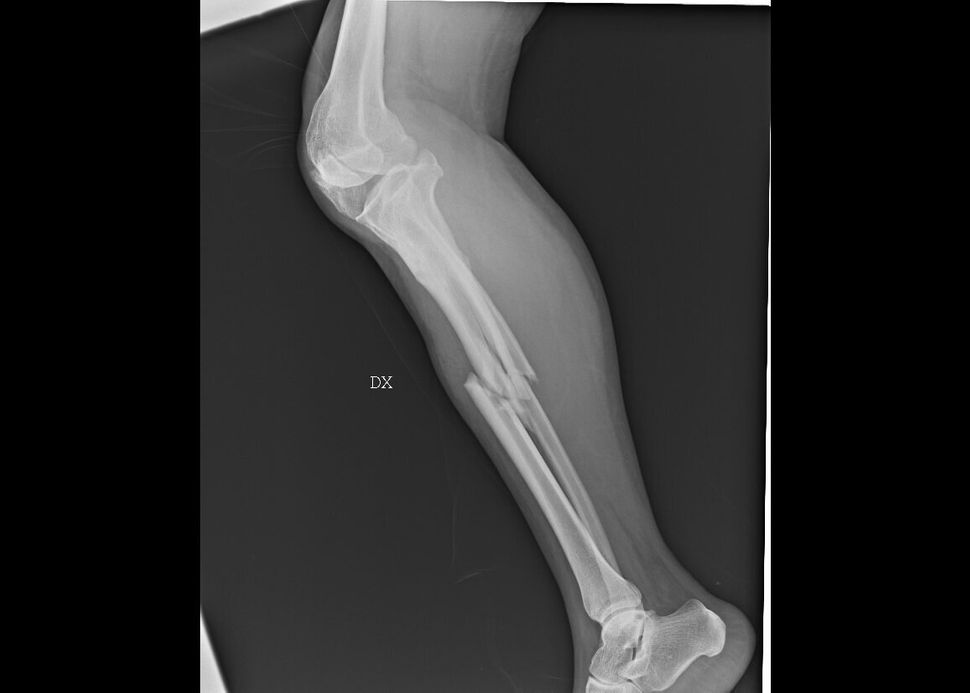

Questa è la storia di una delle protagoniste della mostra “L’invisibilità non è un superpotere”, all’Ospedale San Carlo di Milano dal 21 novembre all′8 dicembre 2019 che, attraverso fotografie e radiografie anonime, racconta il dramma delle donne arrivate nei Pronto Soccorso dichiarando di aver subito violenze, organizzata dall’ASST Santi Paolo e Carlo di Milano e Fondazione Pangea Onlus.

Tra le immagini, oltre alle ossa rotte, si vede un coltello piantato nella schiena.